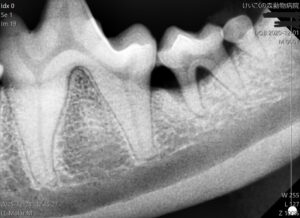

歯のレントゲンを撮ってみると歯周病により歯を支えている骨が溶けているのが分かります。

歯周ポケットが深く、揺れがあり、歯周病が重度に進行している歯は抜歯を行いました。